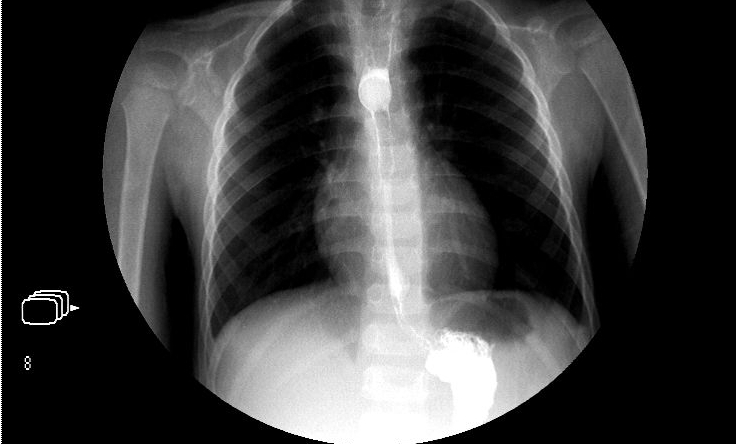

?、谏舷涝煊?。目前許多醫(yī)院均采取了雙重對(duì)比造影的方法,通過口服較少量的鋇與發(fā)泡劑,使鋇劑與氣體形成對(duì)比,更加清晰地勾畫出細(xì)小病變浸潤的范圍,但是對(duì)反復(fù)發(fā)作的十二指腸球潰瘍患者,由于球腔已經(jīng)變形,判斷是否有新的潰瘍出現(xiàn)有一定的困難。